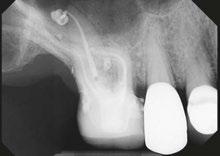

Let’s examine a case of a 58-year-old male who presented to my office in pain. He was referred as an emergency for consultation and treatment on either tooth No. 18 or 19. The patient presented with pain that had been on and off for over a month. The patient’s chief complaint was pain to cold and hot that lingered and now was spontaneous. On examination, tooth No. 19 responded to pulp testing within normal limits and was negative to percussion. Tooth No. 18 had a lingering sensitivity to cold, and a diagnosis of irreversible pulpitis and symptomatic apical periodontitis was made.

As you can see from final radiographs, the GentleWave Procedure’s ability to clean out and clear all portals of exit is on clear display here. I would not have had a similar outcome if I did not use the GentleWave Procedure.

Figure 1: Radiograph of tooth No. 18. The image on the right illustrates how the GentleWave Procedure cleans and clears all portals of exit